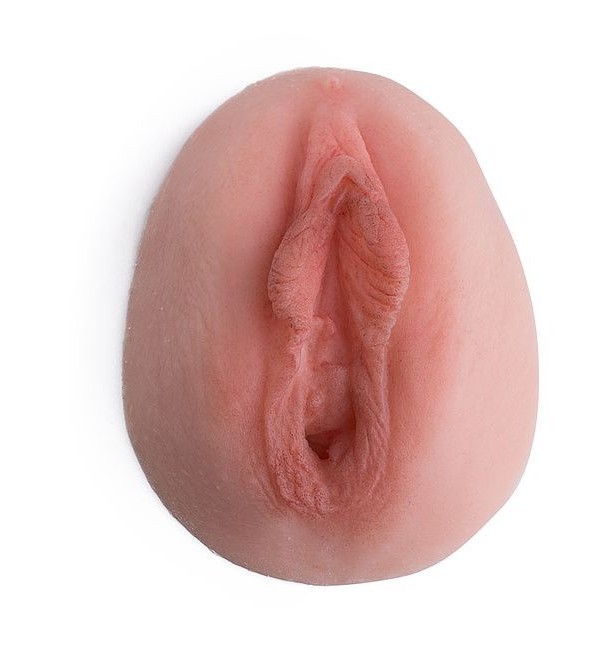

I dilatatori Vagiwell sono dispositivi medici per la dilatazione vaginale in silicone medico, pieni all’interno, in modo da garantire la sufficiente rigidità necessaria all’inserimento ma piacevoli al tatto.

Un’apertura concava ne facilita l’introduzione senza che sia necessario fare leva con un applicatore.